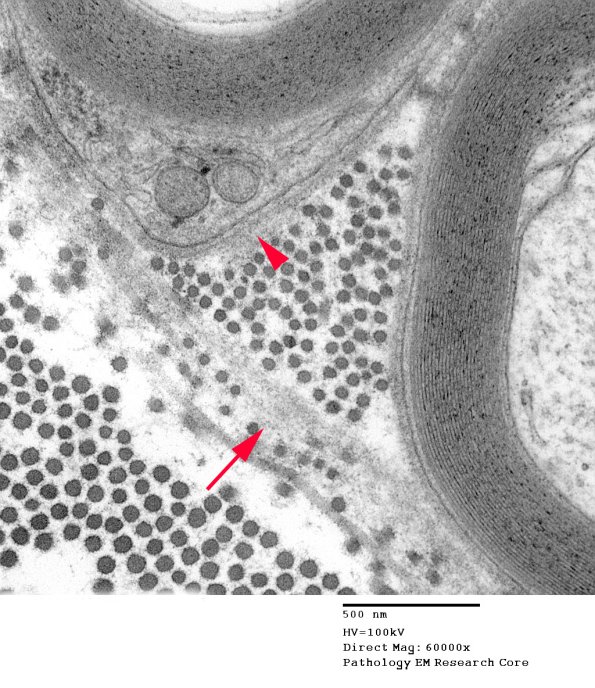

Two magnifications of the final part of the circumference showing the enclosing basal lamina (arrow, 14A8) and the basal lamina intimately applied to the Schwann cell surface (arrowhead, 14A8). (electron micrograph) ---- Comment: This is a classic regenerative cluster; however, often clusters do not retain the parent axon basal lamina for extended intervals. In this case one might wonder if glycation of the basal lamina as part of the diabetic metabolic state has resulted in making it resist the normal process of digestion and turnover.